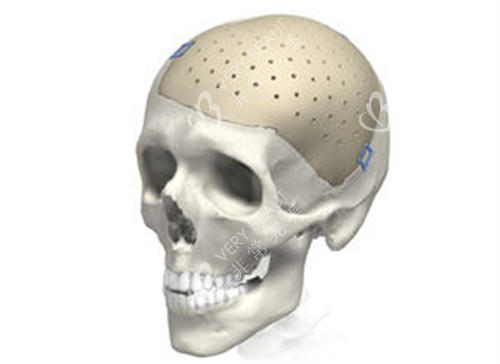

比如颅骨缺损的面积大小、部位形状不同,需要对 PEEK 材料进行个性化切割、塑形,工艺复杂度越高,相关的加工成本就会增加,更终整体费用也会随之变化。

不同患者的颅骨缺损情况不同,材料的厚度、形状是否能更准一些匹配缺损部位,直接影响术后结果和舒适度。